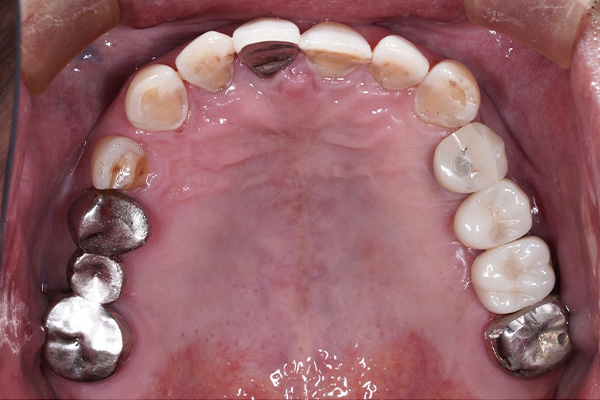

当院では、インプラント治療を行うにあたり歯を失ったところだけではなくお口の中を全体的に検査をします。

その後、コンピューターでシュミレーションを行い、安全でより精度の高いインプラント治療を行っていきます。

インプラントは天然歯よりも感染に弱いため、長く持たせるためにはインプラント周囲の環境を整えることが大変重要になってきます。当院では必要に応じて失われた顎骨・歯肉の再建を行い、予知性の高いインプラント治療を行っていきます。

インプラント治療において私達が大切にしていることは、なぜ歯を失ってしまったかを徹底的に診断することです。

「虫歯で歯を失ってしまったのか?」、「歯周病で歯を失ってしまったのか?」、「かみ合わせの問題があるのかどうか?」等を診断することは非常に大事なことなのです。これらの事は、歯を失ったことは同じですが状況は全く異なるのです。

私達は歯を失ってしまった原因を追求し、インプラント治療、虫歯治療、歯周病治療、矯正治療、根管治療等の治療を組み合わせ総合的に治療計画を立てて治療を行っていきます。